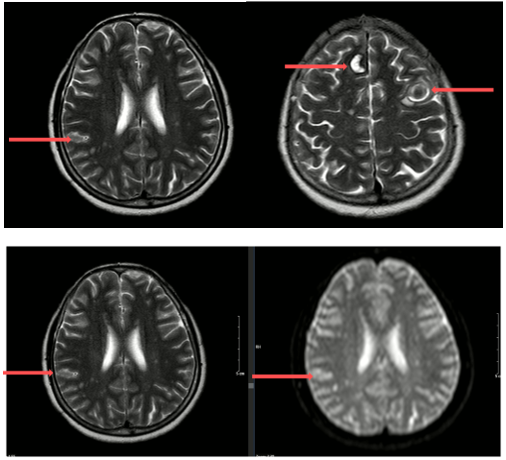

MRI sọ não (05/2024):

Hình 1: Hình ảnh các khối, nốt tổn thương có chảy máu thùy trán phải, góc cầu tiểu não trái, các nốt chảy máu thùy trán trái, thùy thái dương - thùy chẩm phải - theo dõi các tổn thương thứ phát.

MRI sọ não sau điều trị:

Theo dõi định kỳ bằng lâm sàng, chụp CT ngực và MRI sọ não sau 3 tháng, 6 tháng và 15 tháng cho thấy:

- Tổn thương phổi và não giảm kích thước rõ rệt.

- Không xuất hiện tổn thương di căn mới.

- Tình trạng toàn thân ổn định, chất lượng sống được cải thiện.